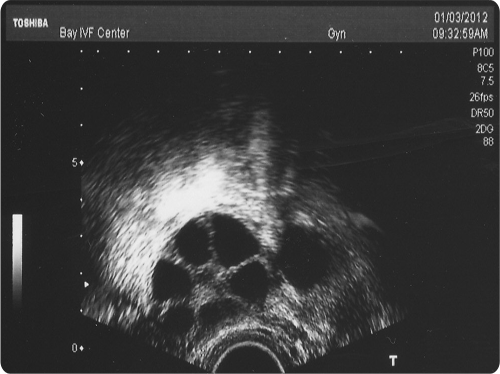

Ovarian stimulation should result in the development of several eggs in each ovary. The ultrasound image below shows a stimulated ovary. Each of the several follicles (dark circles) contains a microscopic egg.